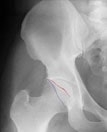

Hip Labral Tears and Femoroacetabular Impingement A Frequent Cause of Non-Arthritic Hip Pain

Hip labral tears have been diagnosed with increasing frequency. In the past, many patients would have unexplained pain stemming from their hip joint.